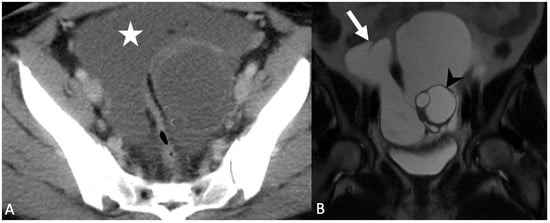

5.1.5. Paraovarian Cyst

5.1.6. Peritoneal Inclusion Cyst